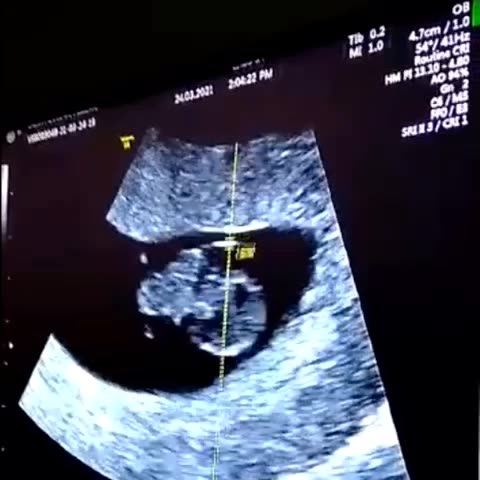

#titia #amor #babona #bebechegando #apaixonada